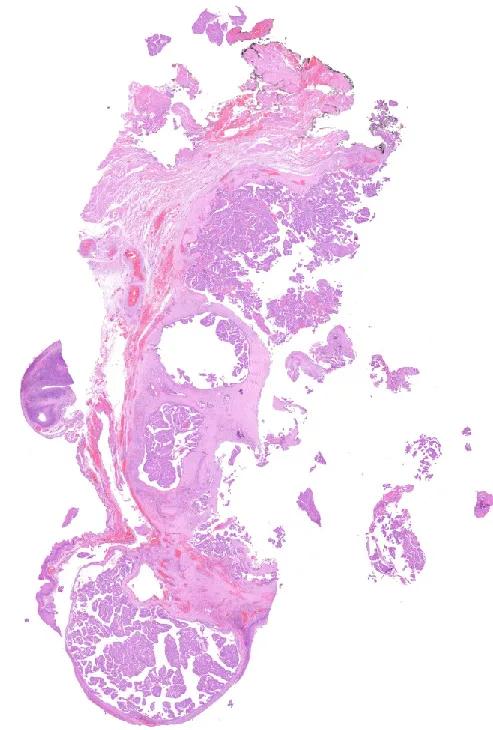

1-H&E1

Diagnóstico: Adenocarcinoma mucinoso, anteriormente denominado cistoadenocarcinoma papilar, de grado intermedio de localización amigdalar.

- Histológicamente se caracterizan por áreas quísticas y sólidas con múltiples proyecciones papilares luminales que tienen un núcleo fibrovascular y están revestidas por células epiteliales cúbicas, columnares o secretoras de moco. Inmunohistoquímicamente es CK7, CEA y EMA positivo, siendo negativo para otros marcadores de glándula salival. (PMID: 35252049)